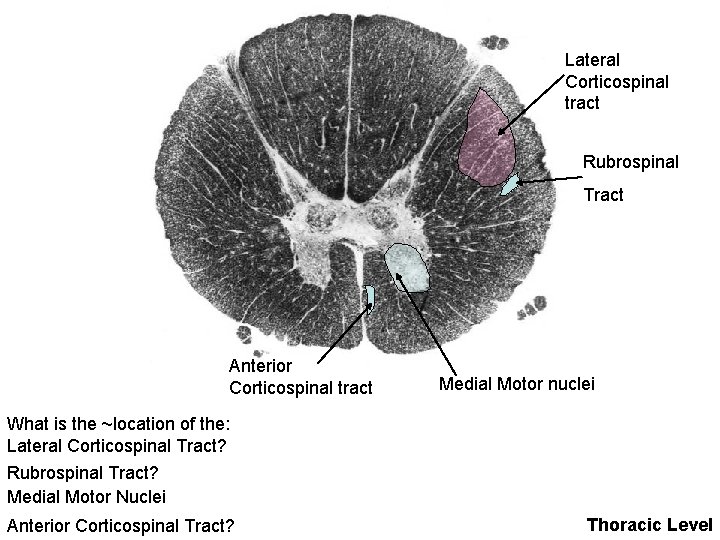

Lateral Corticospinal tract Rubrospinal Tract Anterior Corticospinal tract Medial Motor nuclei What is the ~location of the: Lateral Corticospinal Tract? Rubrospinal Tract? Medial Motor Nuclei Anterior Corticospinal Tract? Thoracic Level